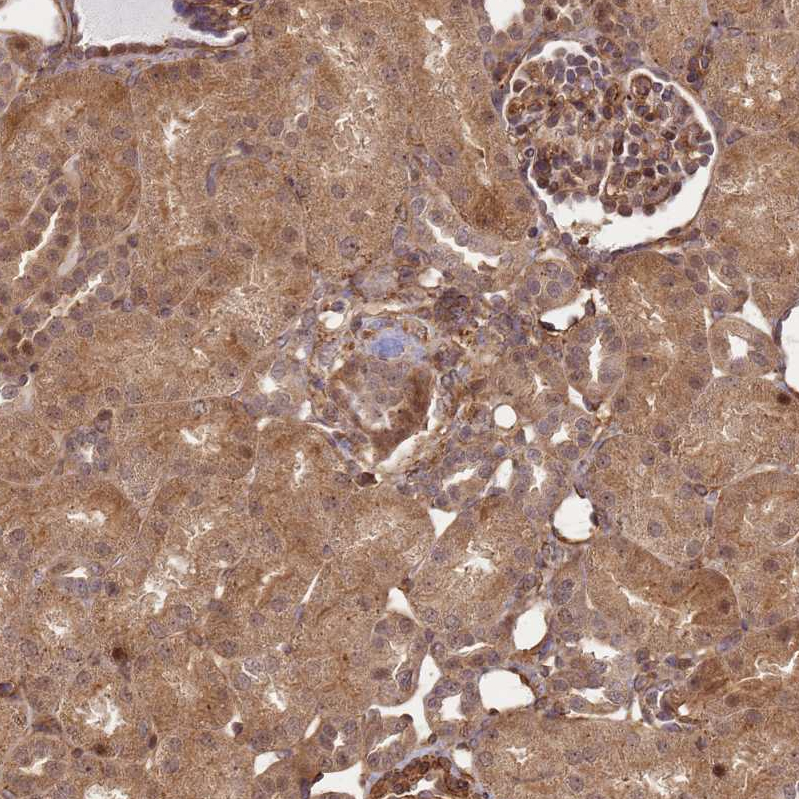

Immunohistochemical staining of human placenta shows strong cytoplasmic positivity in trophoblastic cells and endothelial cells.